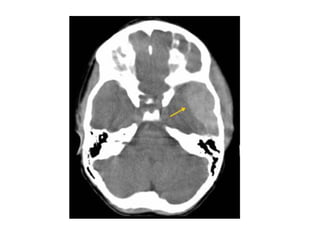

Lateral lenticulostriate infarction , note the inverted comma-shaped

hypodense left lenticular nucleus (red dotted lines) , the anterior limb of

the left internal capsule (yellow arrow) is also involved by the ischemic

infarction while the head of the left caudate nucleus (blue dotted lines) is

spared